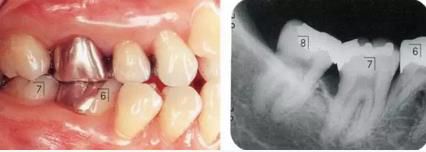

360截圖20170422101945505.jpg

▲圖9-1,2

▲圖9-1 預(yù)定進行正畸治療的患者,下頜磨牙區(qū)的右下6,7牙根接近,并在右下7遠(yuǎn)中存在垂直性骨組織缺損。對牙體狀況、牙周組織、咬合情況進行診斷后制定出的治療方案為:將右下6拔除,對右下7遠(yuǎn)中的骨組織缺失進行再生療法。

▲圖9-2 同部位X光片。右下6遠(yuǎn)中存在牙根接近,較深的骨組織缺損以及II度根分叉病變,所以將其拔除。

360截圖20170422101957225.jpg

▲圖9-3

拔牙后1周的狀態(tài)。愈合后,預(yù)定進行正畸治療穩(wěn)定牙列。